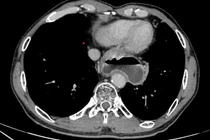

Nuốt nghẹn, ợ chua, sút cân,... người đàn ông 70 tuổi (Hà Nội) đến bệnh viện khám bất ngờ phát hiện ung thư thực quản nghi ngờ di căn phổi. Đặc biệt, trước đây 10 năm ông đã từng phải phẫu thuật cắt 3/4 dạ dày vì ung thư.